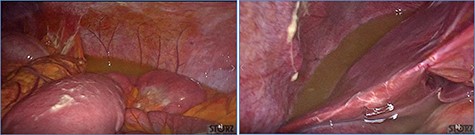

Progressive small bowel revascularization perceived by slow reappearance of vasa recta after peritoneal lavage.

fluid collection in the peritoneal cavity. Subsequent CT confirmed the presence of diffuse fluid collection in the peritoneal cavity (Fig. 1) but no free air, with distention, bundling and thickening of some small bowel in the left quadrant (Fig. 2). The patient was therefore admitted for supporting therapy (intravenous fluids and antibiotics) with the suspicion of cocaine-induced small bowel ischemia. Twelve hours later, signs and symptoms of diffuse peritonitis developed: worsening diffuse abdominal pain with rebound guarding at examination, a significant increase in WBCs count (16.15 × 103/μl) and neutrophilia (88%), lengthening of coagulation times (INR: 1.68; aPTT: 33.0 s) and increase in fibrinogen (430 mg/dl) and D-Dimer (2275 ng/ml). Therefore, urgent surgical exploration of the abdomen through a three-port open laparoscopic approach was performed, confirming the presence of 1200 ml of exudative fluid and fibrin clots (Fig. 3). Several adhesions between greater omentum, abdominal wall and small bowel underwent blunt dissection. Thorough exploration of the small bowel revealed two ischemic segments located at about 50 and 100 cm from the Treitz ligament (Fig. 4). The large bowel appeared normal. The existence of non-visible gastro-duodenal perforations was ruled out with the administration of 500 ml of saline with 20 ml of methylene blue through the nasogastric tube. An iv bolus of sodium heparin, 10 000 IU, was then administered, performing a 30-min peritoneal lavage with 5 l of saline solution at 37°C. After reaspiration of peritoneal lavage, a new complete exploration of the small bowel was performed, showing complete revascularization of the two ischemic small bowel segments (Fig. 5). Two tubular drainage tubes were placed in the left and right colic gutters. Culture examination of peritoneal exudate was positive for multi-sensitive Escherichia coli and Enterococcus, thus confirming bacterial translocation peritonitis. Postoperative therapy included the administration of iv piperacillin–tazobactam and subcutaneous low molecular weight heparin. Postoperative recovery was smooth, with oral feeding on the second postoperative day (POD), drainage removal on POD 3, complete bowel function restored on POD 4 and home discharge on POD 5. At 15- and 30-day-follow-up, the patient showed full recovery, being now followed by a specialized support structure for his drug abuse.